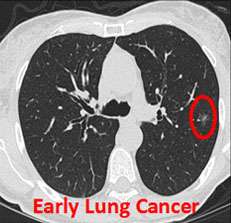

Lung Cancer Screening

Screening is looking for cancer before a person has any symptoms. UCLA is a leading institution in lung cancer screening. The recommendations for lung cancer screening are based on a several studies that carefully evaluated low-dose CT scanning to look for lung cancer in high-risk patients. The most significant study was the National Lung Screening Trial (NLST).

The benefits of lung cancer screening include:

- Early detection of lung cancer

- Decreased mortality from lung cancer

Lung Cancer & NSCLC Diagnosis

In addition to a physical examination, laboratory tests and imaging studies are needed. These tests include:

- CT scan